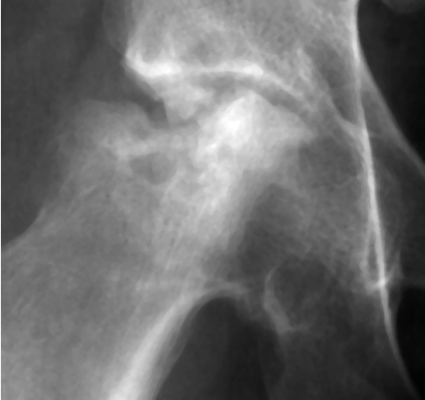

One image each of two separate patients with collapse and necrosis of the femoral head, both of which are secondary to repeated injection of steroids. A rapid progression of change in a joint secondary to steroid injections. Transition of a joint from one of minor alterations(such as narrowing, sclerosis) to one of significant bony fragmentation and collapse. Gouged-out areas of bony destruction may be similar to small animal bites, hence the bite sign.

AP hip - Click on the image for a larger versionA - Click on the image for a larger versionB